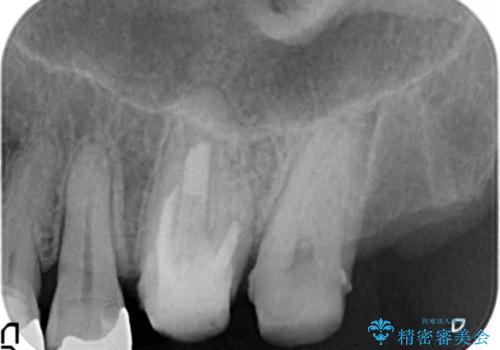

- 失ってしまった左下の奥歯にインプラント治療を受けたいと来院されました。

左下の欠損部には強度・表面性状に優れるストローマン社製インプラントを埋入し、合わせて噛み合う上顎の歯もクラウン再補綴による整備を行い安定した咬合関係の構築を目指します。

歯を失った期間が長くなると、対合する歯が伸びてくることによる補綴スペースの狭小化がしばしば見られます。

今回左下にインプラント治療を行うにあたり、対合する上顎の歯もいっしょに治療を行ったことで安定した咬合関係を構築することができました。